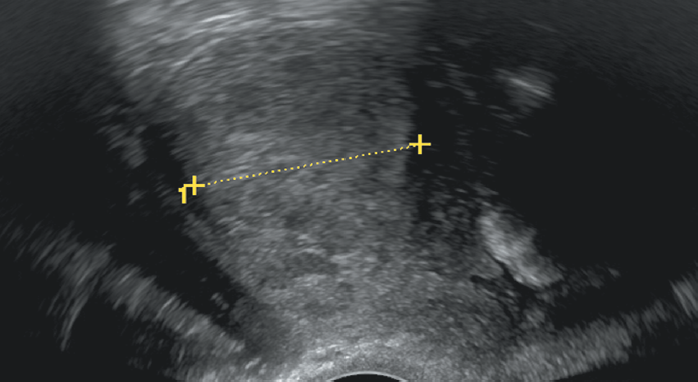

При трансвагинальном УЗИ эстрогеноподобное действие тамоксифена (развитие кистозной атрофии эндометрия) проявляется увеличением толщины эндометрия за счет стромальной пролиферации, возникновением субэндометриальных кист, неровностью границы эндометрий/миометрий, эндометрий приобретает вид «пчелиных сот» (рис. 1) [18, 19].

Рис. 1. Пациентка Н., постменопауза 9 лет. Прием тамоксифена 3 — года 5 месяцев. Толщина эндометрия — 10 мм. Структура эндометрия — гиперэхогенная, с щелевидными кистозными включениями. Эндометрий — аваскулярный. Визуализируются субэндометриальные кисты. Граница эндометрий/миометрий — нечеткая (кистозная атрофия эндометрия)

Fig. 1. Patient N., 9 years postmenopausal, after 3 years 5 months of Tamoxifen therapy. Endometrial thickness = 10 mm. The structure of the endometrium is hyperechogenic, with slit-like inclusion cysts. Endometrial tissue is avascular. Subendometrial cysts are visualized. The endometrial-myometrial border is blurred (cystic endometrial atrophy)